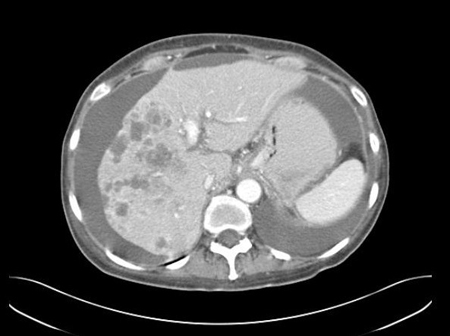

[Figure caption and citation for the preceding image starts]: CT abdomen with intravenous contrast, revealing numerous enhancing lesions in right hepatic lobe, with associated ascites; percutaneous biopsy of one of these lesions revealed adenocarcinoma, but no primary site was identified during routine work-up: a typical presentation of ACUPFrom the personal collection of Dr D. Cosgrove [Citation ends].